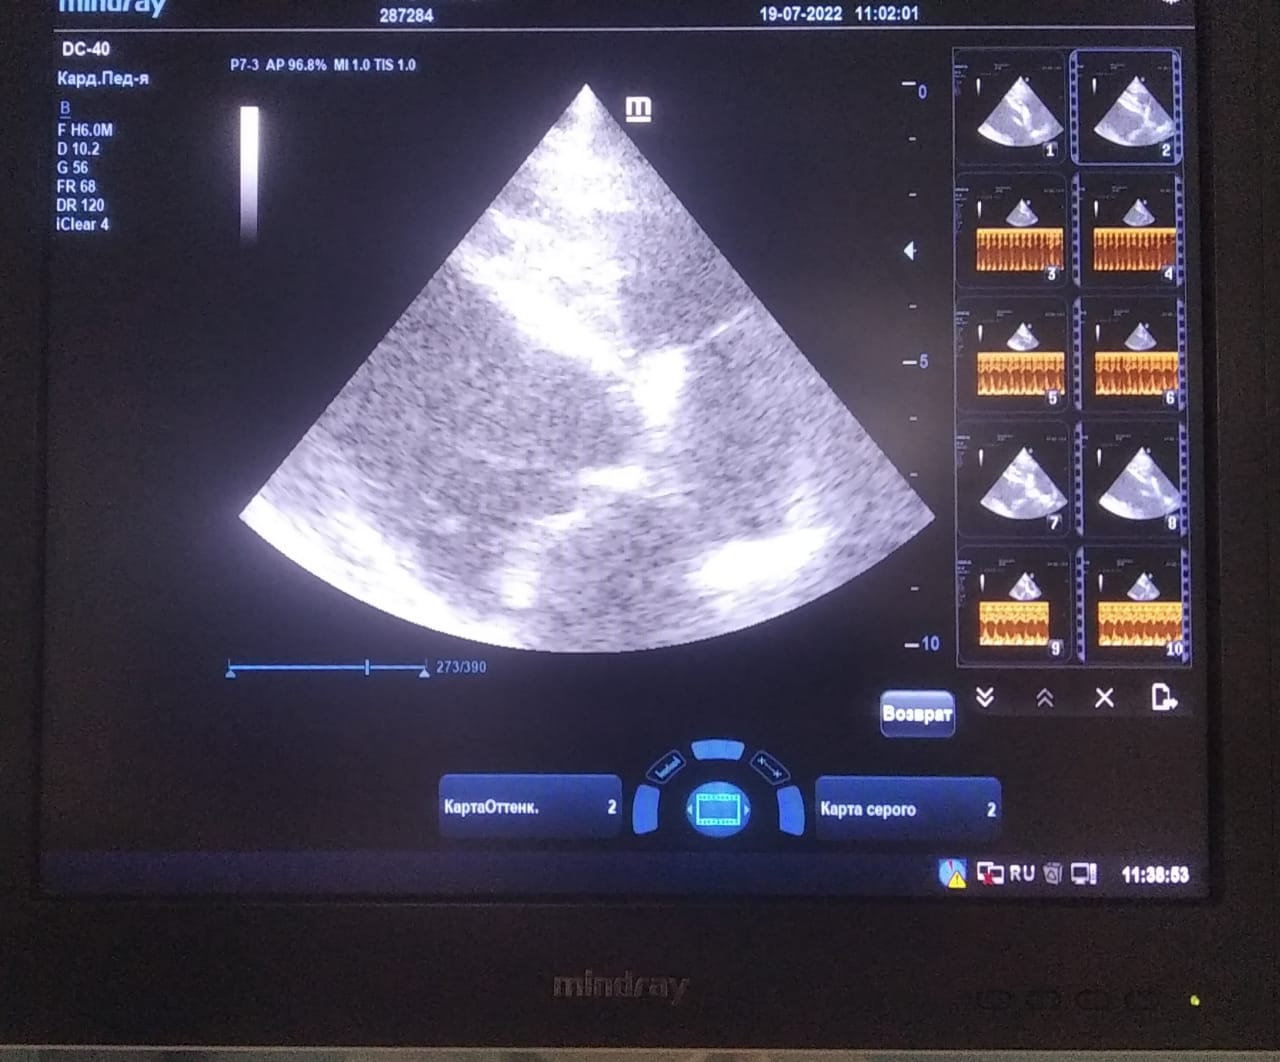

Хорошо бы рентген легких и эхо сердца.

Сегодня Арчуна Ирина возила на рентген легких и сдали анализ мочи. Результат анализа мочи готов будет завтра. Рентген легких выставляю.

Ирина, ждем твоего вердикта по рентгена и можно ли нам готовить Арчи к операции по глазам.

Глаза наверное можно делать, но лучше после спада жары. Все таки легкие еще не в норме.